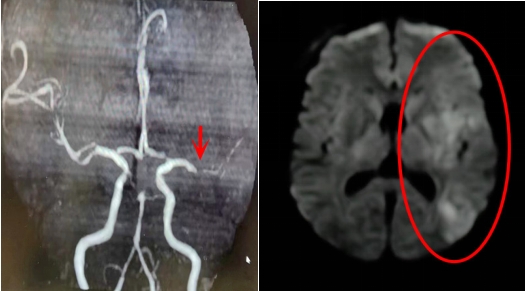

卒中中心醫護人(rén)員(yuán)向醫務科(kē)報告情況後,對患者予以靜(jìng)脈溶栓治療。從(cóng)患者進入我院到開始靜(jìng)脈溶栓,DNT時間(指從(cóng)患者發病入院到使用溶栓藥治療的這一時間)爲40分(fēn)鍾。當班醫生(shēng)立即爲患者進行核磁共振血管評估,結果顯示:責任血管左側大(dà)腦中動脈嚴重狹窄,遠(yuǎn)端分(fēn)支減少。

1小時後,患者意識恢複清醒,且肢體(tǐ)能夠在床面上活動。經過進一步治療,患者的語言障礙和肢體(tǐ)無力症狀得(de)到明顯改善, CTA評估提示血管再通。